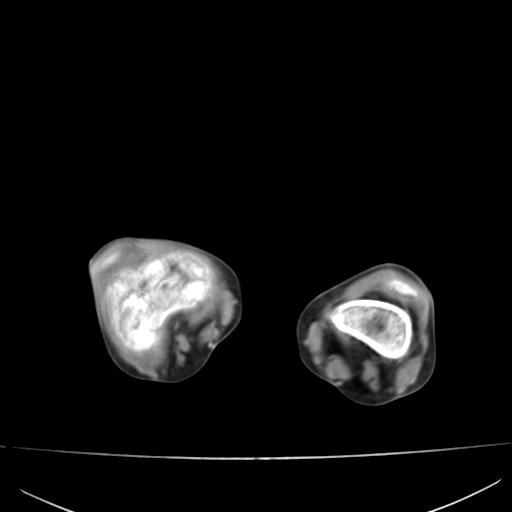

标题: PED0940:M12Y,左股骨下端酸痛畸形 [打印本页]

标题: PED0940:M12Y,左股骨下端酸痛畸形

12岁男孩,左膝关节肿痛8年,近月明显

内生骨软骨瘤?

血友性关节病?